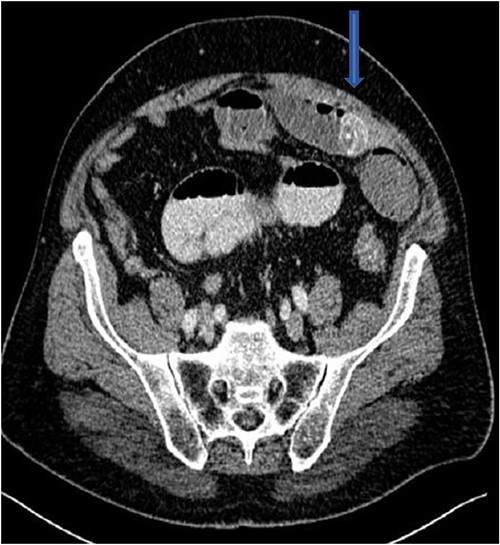

The plain film of the abdomen showed multiple air-fluid levels on the erect film (Fig. 1) and small bowel dilatation on the supine (Fig. 2). The CT showed multiple air pockets in the biliary tree, representing pneumobilia (Fig. 3). It also showed evidence of a circular radio-dense stone measuring 2 cm within the distal jejunum, leading to obstruction and dilatation of the proximal jejunum (Fig. 4).

Gallstone ileus occurs in 0.3%–0.5% of patients with cholelithiasis [3], and it accounts for 25% of mechanical obstruction of the small bowel in patients over the age of 65 [4]. The stone gets access through a fistula between the gallbladder and part of the bowel. Commonly, it gains access through a cholecysto-duodenal fistula in 68% of patients with gallstone ileus [5]. It can rarely gain access without a fistula by means of a stone passing through the ampulla of Vater, followed by in-situ growth [6]. Once it gains access, it can lodge in any part of the bowel. The terminal ileum is the commonest site, being the narrowest [1]. The second-commonest is the jejunum, at 30% [7]. Less commonly, lodgment of the stone in the duodenum (3%–10%) gives rise to Bouveret’s syndrome, leading to gastric outlet obstruction [3].

CT is the investigation of choice. Plain films can reveal dilated small bowels, confirming small bowel obstruction [8]. The presence of Rigler’s triad on the plain film, which includes pneumobilia, dilated bowel, and ectopic gallstones, is diagnostic of gallstone ileus, but this occurs only in 9%–14% of patients [7]. Most patients require surgical intervention to relieve the obstruction. Surgery includes enterotomy and removal of the stone (enterolithotomy) or enterolithotomy with cholecystectomy and repair of the fistula [2]. Commonly, simple enterolithotomy is favored as it carries less morbidity, with or without cholecystectomy at a later date [9]. Spontaneous fistula closure occurs in up to 50% of cases [7].